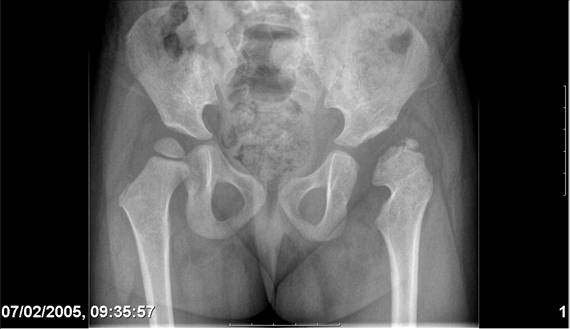

[Ortho] Врожденный вывих бедра

Navernoe Dega

Chto by ne byt goloslovnym posilau vam svoi sluchai gde sdelal vse chto napisal vyshe

Mark Eidelman